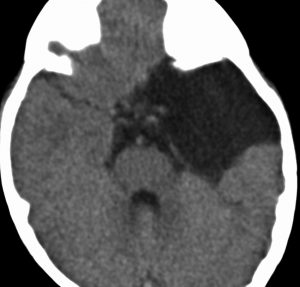

中頭蓋窩・症候性・くも膜のう胞

60代の女性で偶然発見された大きなクモ膜のう胞です。経過とともに少しづつ増大して,ふらつき,眠気,気分の落ち込みなど抑うつ状態となりました。抗うつ薬の投与が開始され増量されましたが精神症状は悪化して何もできなくなりました。おそらく右側頭葉症状として抑うつ症です。内視鏡ですと脳に損傷が生じますから,開頭顕微鏡手術で,クモ膜のう胞を脳底槽へ開窓しました。術後に症状は消失して5年になりますが,抗うつ薬なしで元気にしています。

もしかするとこれは,巨大な choroidal fissure cystかもしれません。